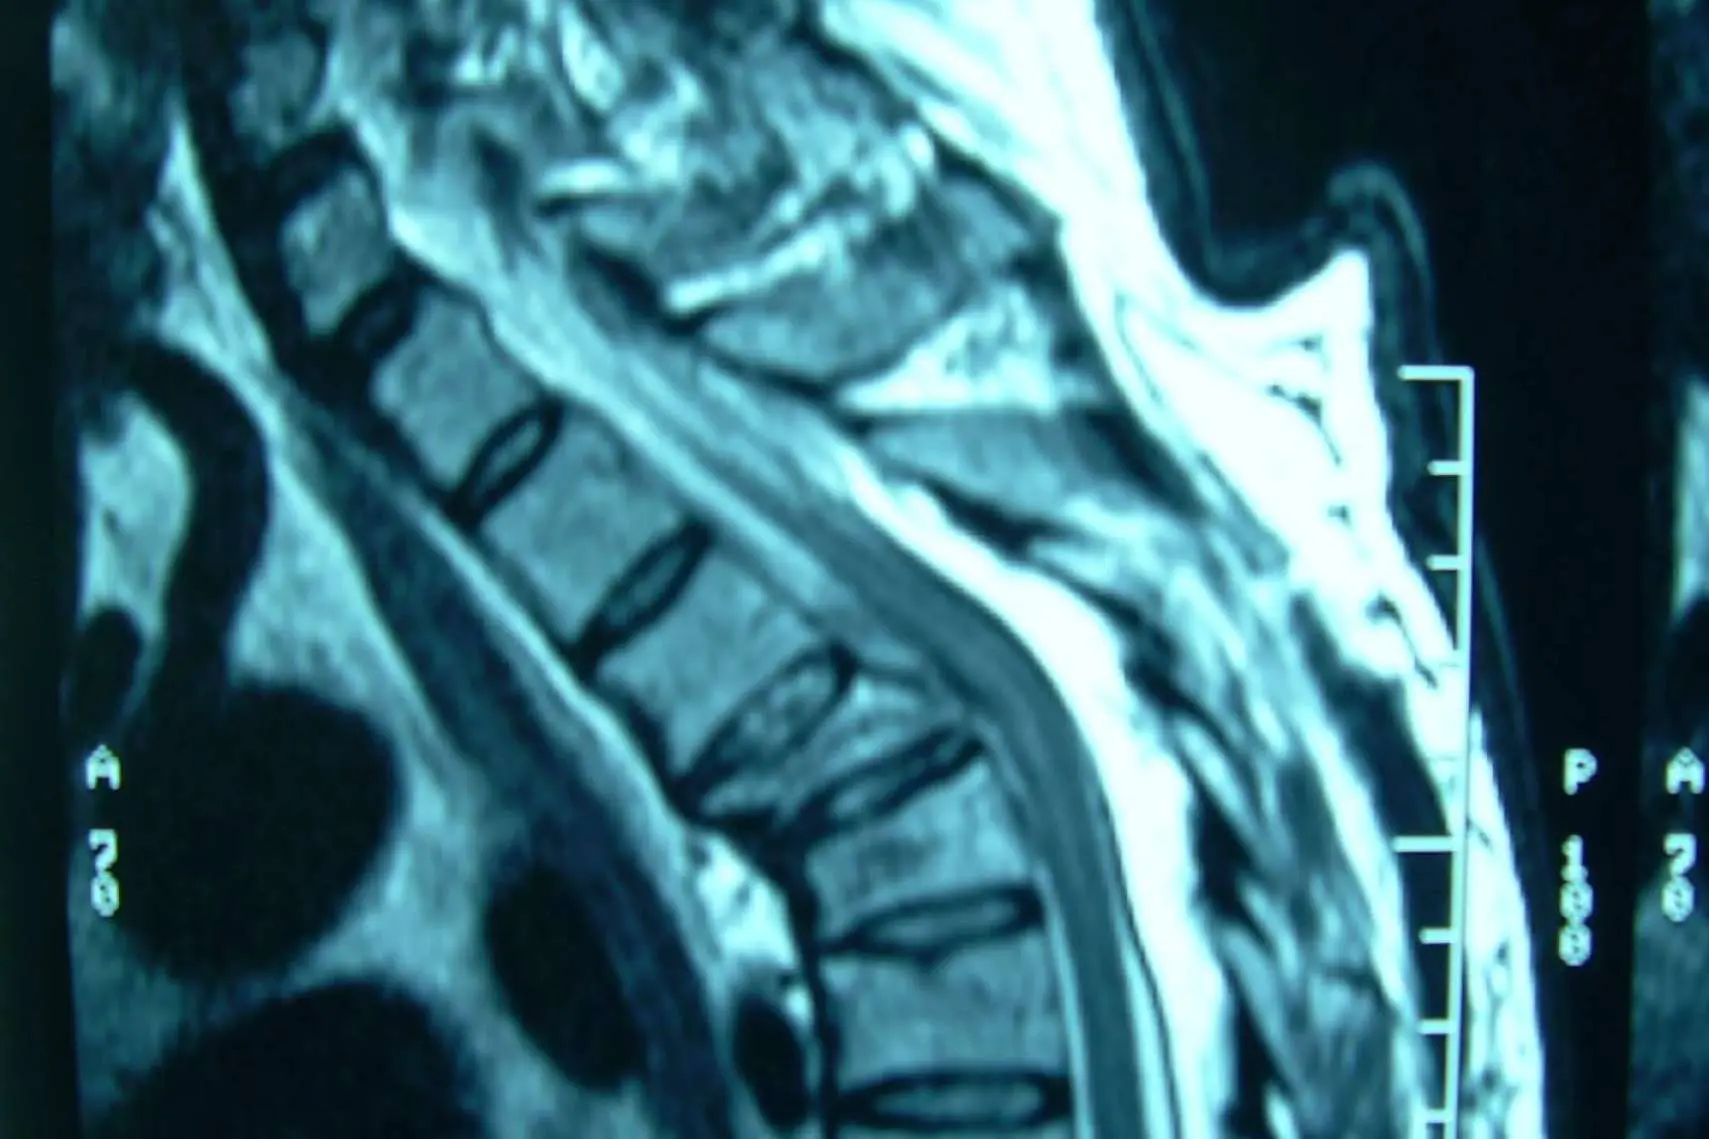

Las fracturas vertebrales son la ruptura en cualquier vértebra de la columna y, dependiendo de la localización de la parte afectada, pueden traer secuelas en la zona cervical, torácica, lumbar, del sacro o del coxis.

Los dolores de fractura de la columna pueden deberse a la ruptura del hueso que puede manifestarse en el sitio de la lesión o a la distancia por algún nervio comprometido. También pueden ser por dolor neurológico que indica una mayor alerta porque compromete la parte sensitiva o motora, evidenciando que hubo un desplazamiento que está afectando la médula espinal. De cualquier forma, un especialista como los cirujanos de Neurocirugía Galarza deberá revisar al paciente y hacer un diagnóstico por medio de estudios específicos para definir cómo proceder.